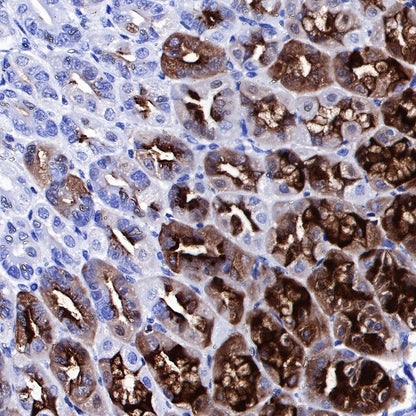

IHC shows positive staining in paraffin-embedded rat stomach. Anti-PG II/PGC antibody was used at 1/1000 dilution, followed by a HRP Polymer for Mouse & Rabbit IgG (ready to use). Counterstained with hematoxylin. Heat mediated antigen retrieval with Tris/EDTA buffer pH9.0 was performed before commencing with IHC staining protocol.